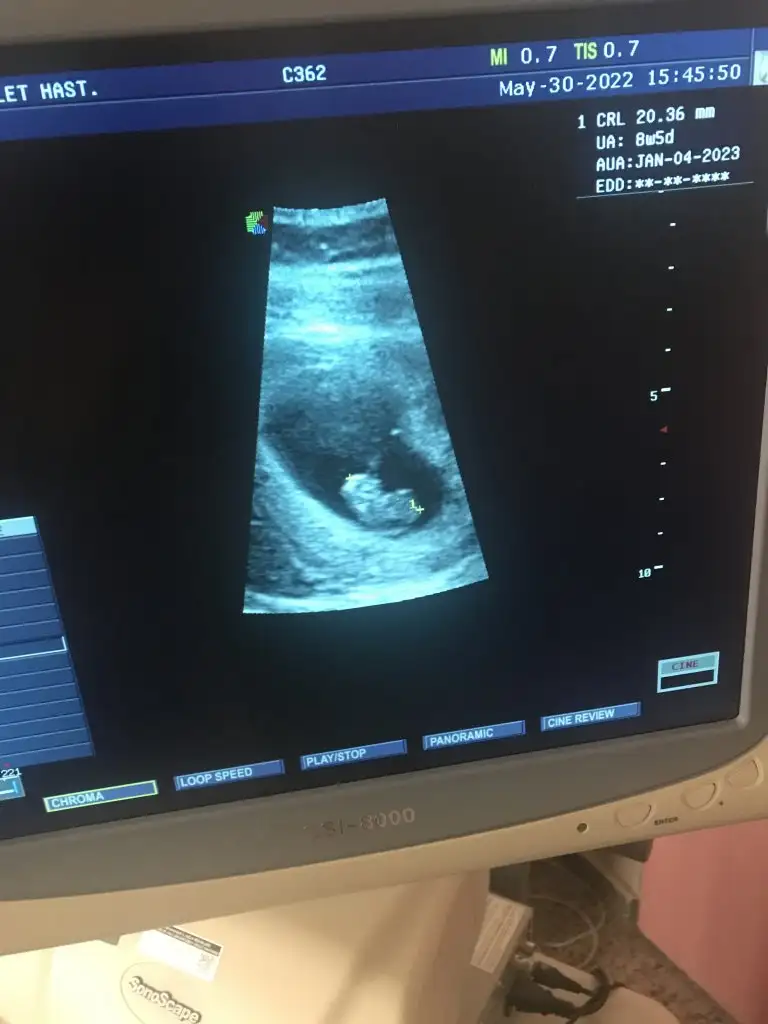

Benimkinide tahmin edebilirmisiniz lutfen 8 hafta 5 gun